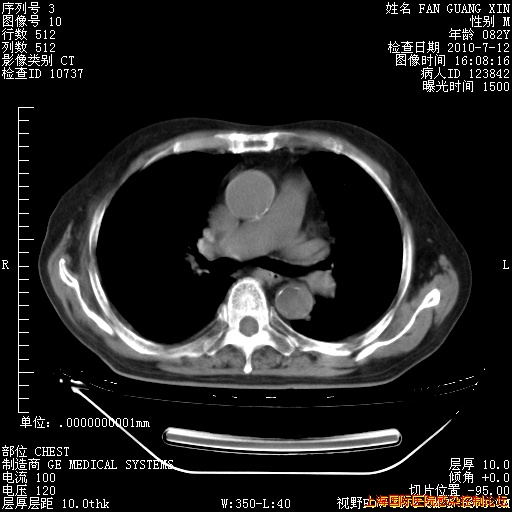

6月12日纵膈窗

6月10日改甲强龙80mg qd ,在南京年会期间体温不稳,18日有一次寒战后体温达39度。19日开始用甲强龙60mg bid ,加量后第二天就不发热。本打算在两周后即7月3日减量,但是7月2日洗澡受凉、发热、咳嗽、鼻音,口服复方大青叶片,甲强龙120mg用到9日(整整20天)。

自昨天起甲强龙改为80mg qd。

在抗结核治疗2周后一般情况逐渐好转。